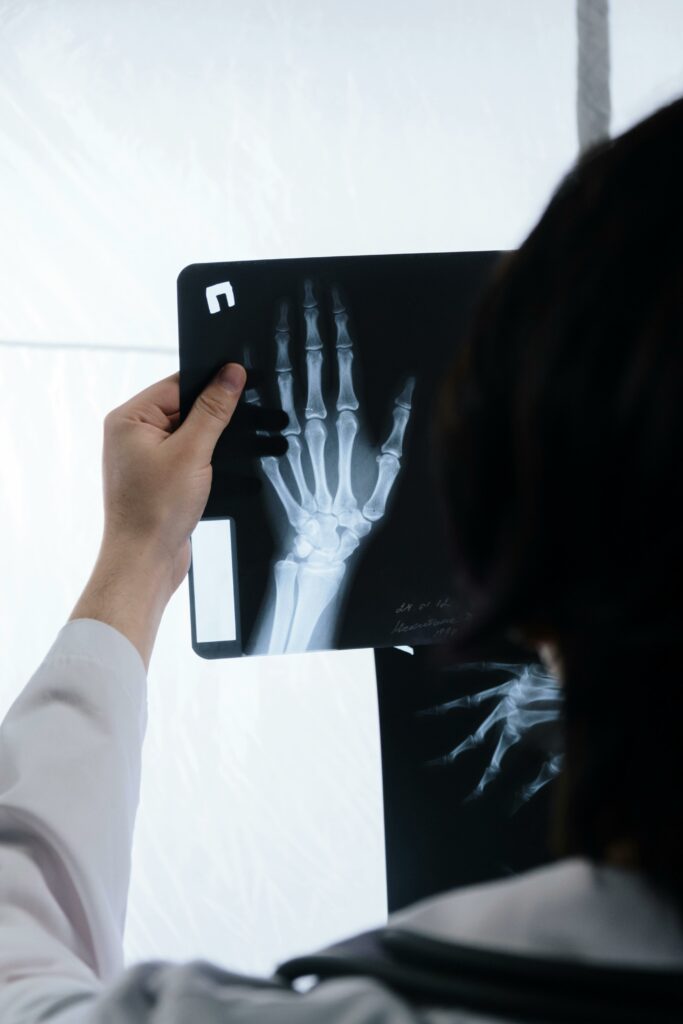

Radio Poignet et Main

Main et Poignet

La main et le poignet forment un ensemble complexe de os, articulations, tendons et ligaments, permettant des mouvements précis et une grande dextérité.

• Le poignet relie la main à l’avant-bras et assure la mobilité globale.

• La main contient les os du carpe, les métacarpiens et les phalanges, ainsi que de nombreux tendons qui contrôlent chaque mouvement des doigts.